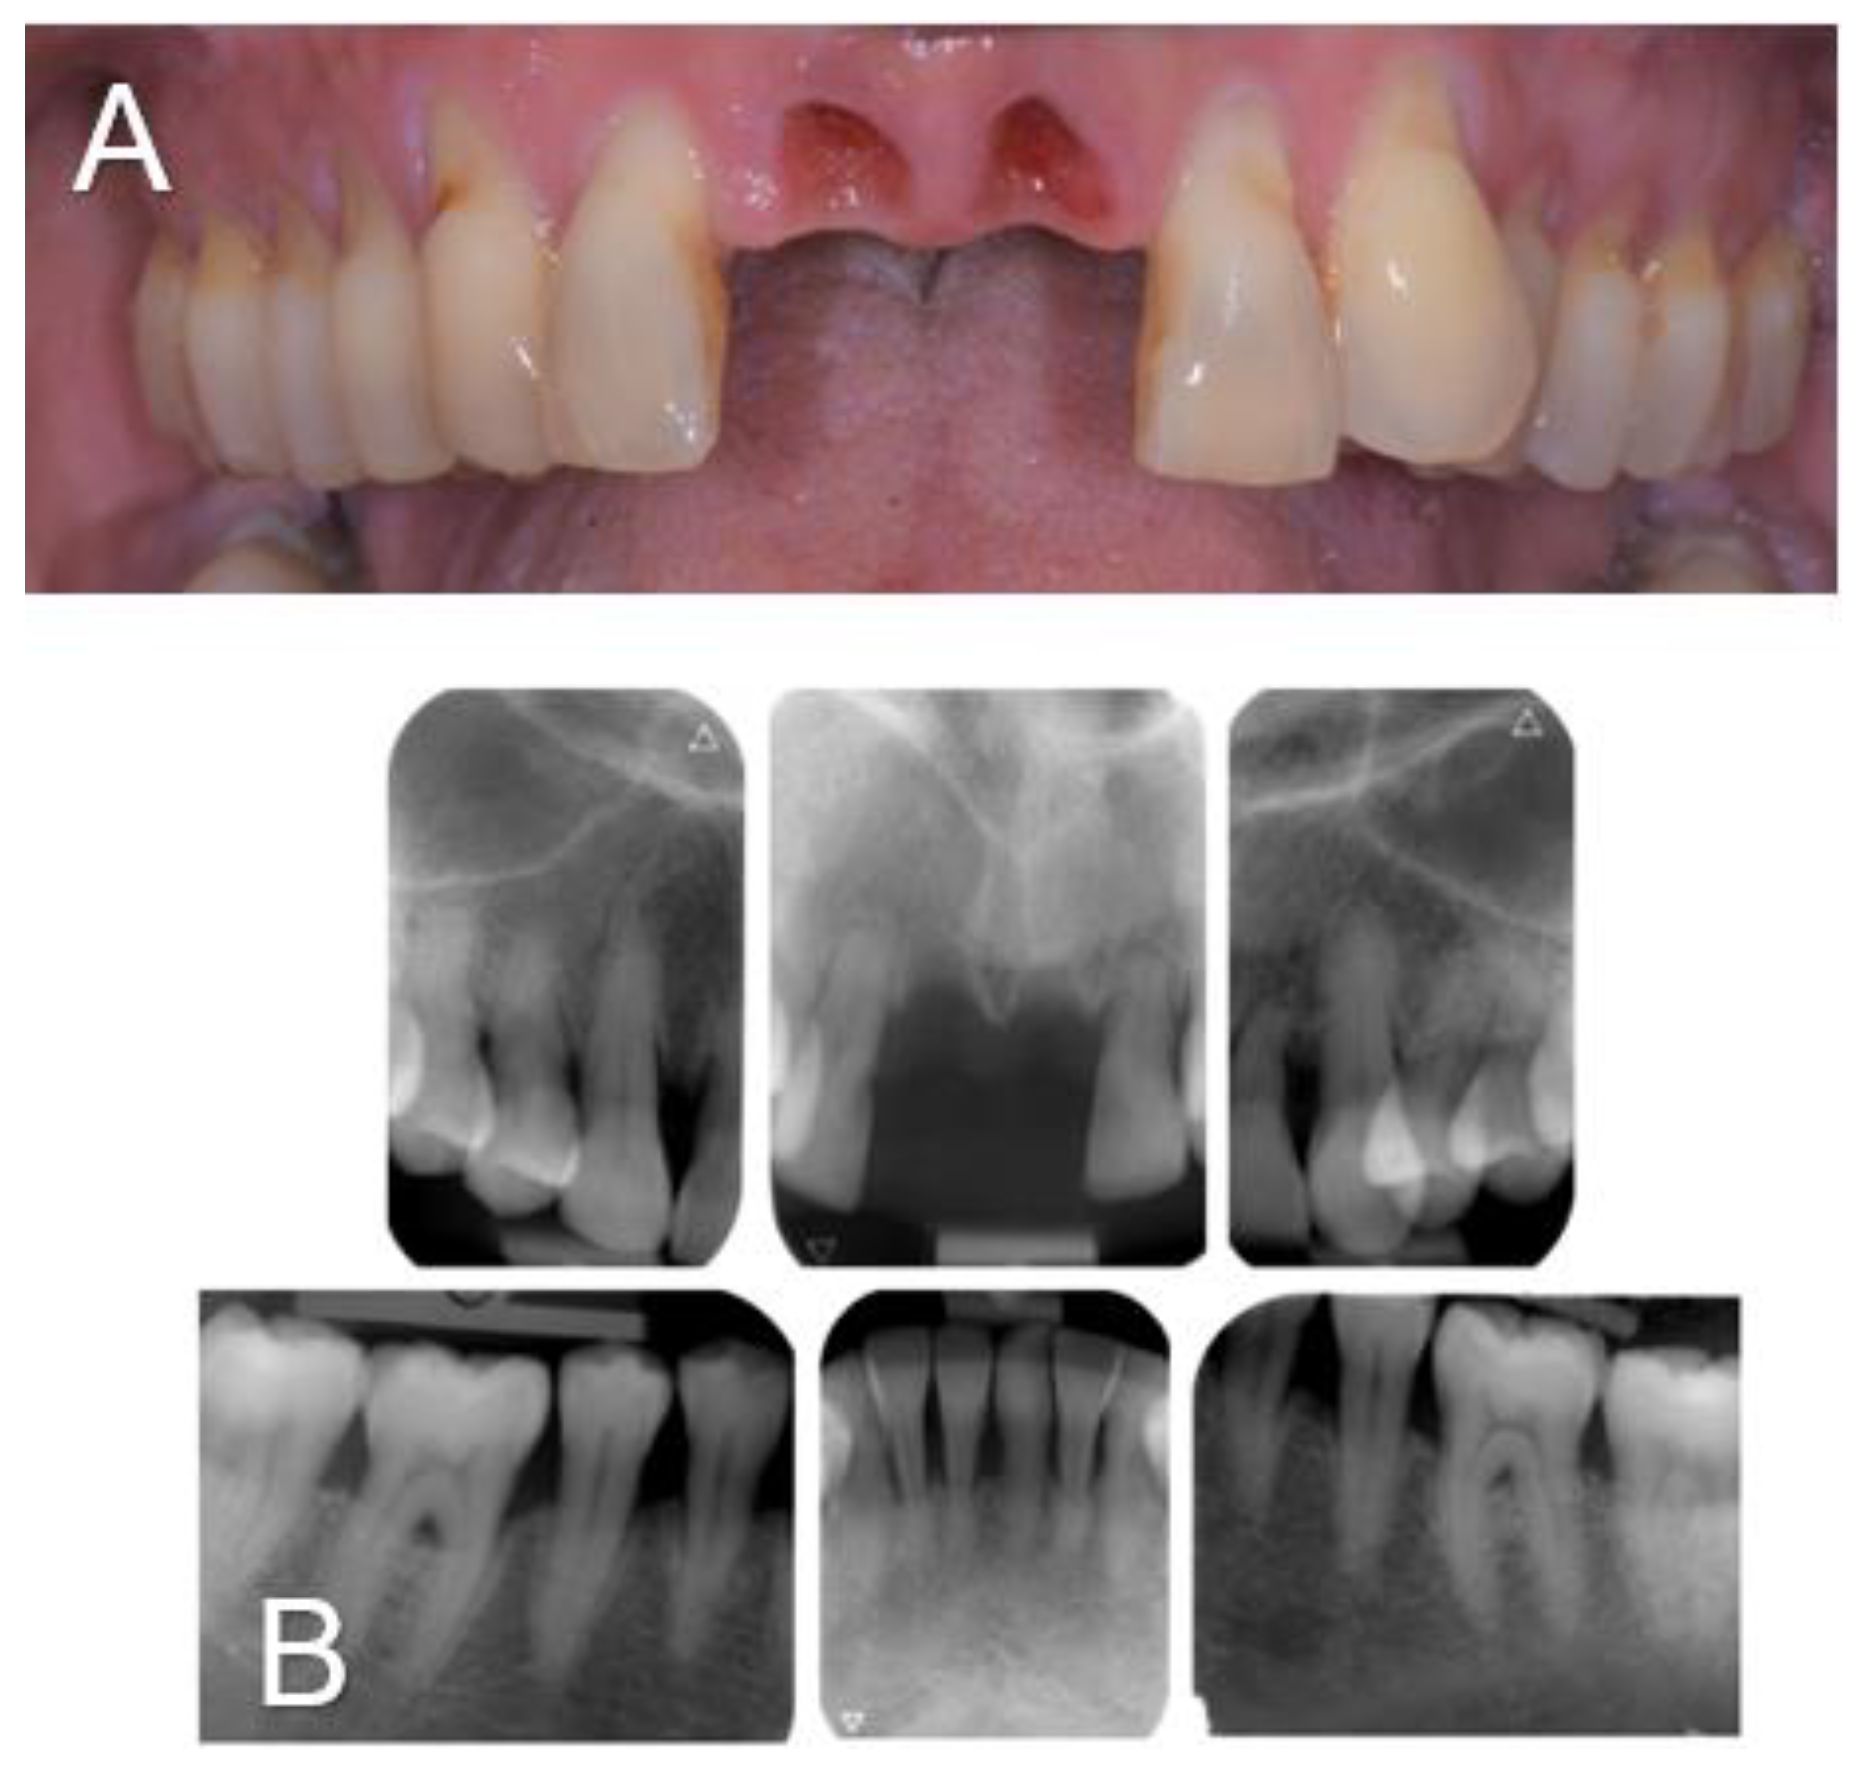

A 61-year-old woman was referred to the Oral Surgery and Implantology Unit of the University Hospitals of Geneva for treatment of edentulous sites after dental avulsions of teeth 11 and 21 following traumatic shock due to endotracheal intubation under general anesthesia performed to remove a laryngeal cyst. Past medical history was significant for pharyngeal dysesthesia and a supraglottic cyst. The dental history revealed that the patient had a history of chronic generalized periodontitis treated few years earlier. Clinical and radiological examination showed generalized bone loss especially at the edentulous sockets 11 and 21 and adjacent teeth 12 and 22.

Figure 1. Clinical view (A) and intra-oral radiographs (B) showing the initial clinical status after dental avulsions due to endotracheal intubation as well as the severe chronic periodontal disease.